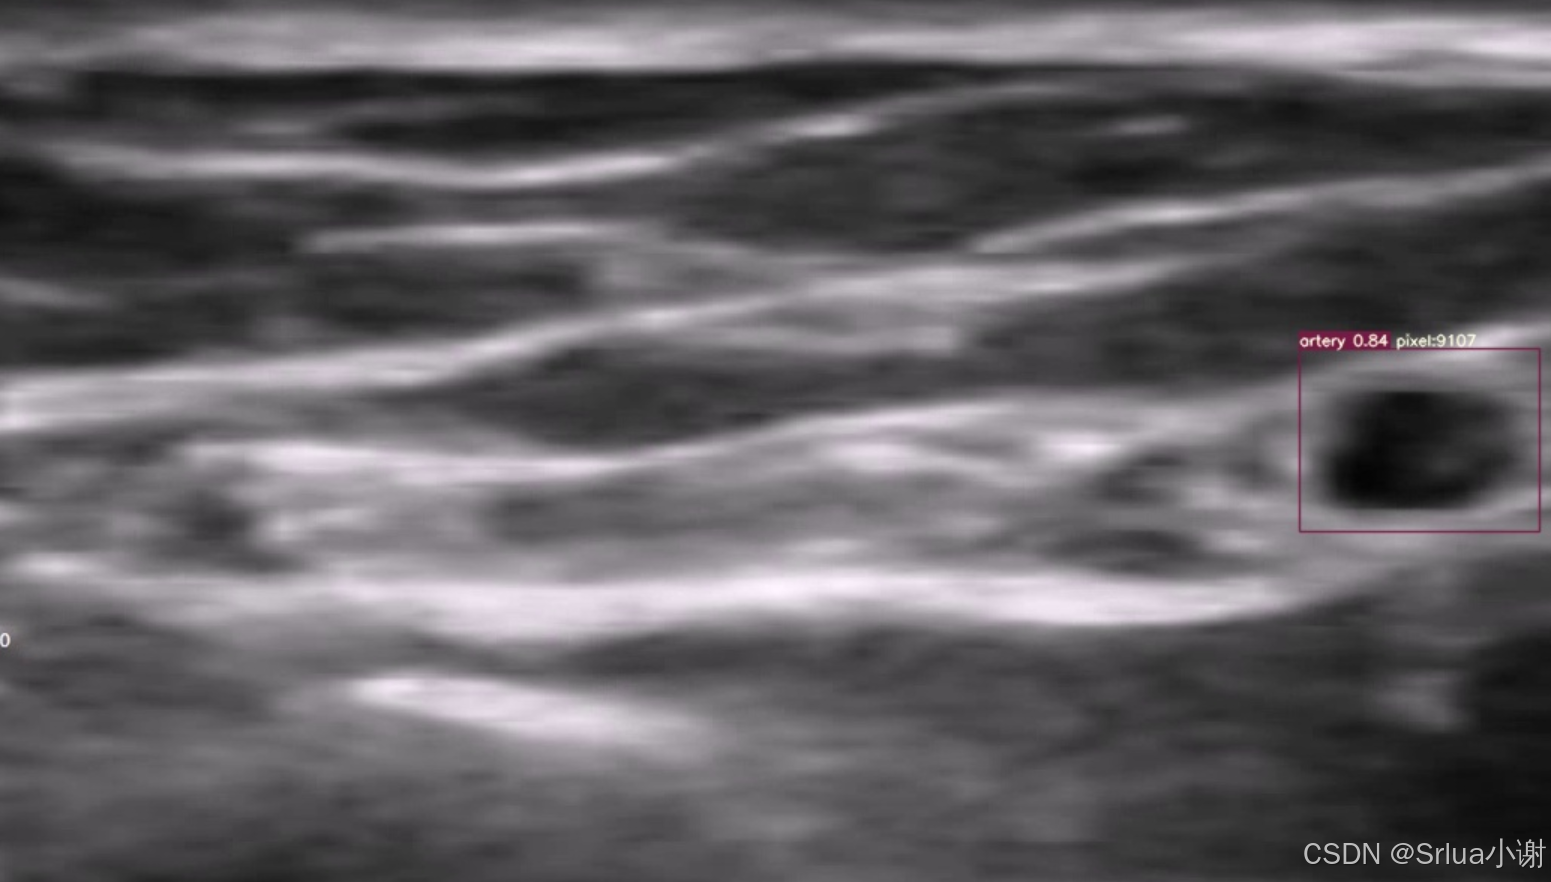

全自动的超声图像动脉血管弹性分析首先应该将动脉血管检测出来,检测出来之后,我们才能对其进行定位,并分析其弹性。在这里我们提供了一些手臂动脉血管的超声图像以及视频,经过图像增强后并打上了标签,检测模型采用的时YOLOv7-tiny,经过训练之后可以获得一个比较精准的动脉血管实时检测模型。

检测效果如图苏所示。

首先我们来说清楚什么是血管弹性分析。血管弹性就是血管收缩后能否再次扩大的能力,一般老年人的血管弹性较差,在病人接受检查时,超声探测头放在病人手臂上,看到的是病人的手臂横切面,所以动脉是呈现出一个类似于圆形的状态,也就是上面图片中检测到的东西。动脉在不停的收缩,所以这个圆的半径是不停的放大缩小放大缩小的。如何判断其弹性呢?一般在接受检查时,首先计算其动脉的半径变化,接着会在病人的胳膊上绑上一个橡胶带,让血管收缩,这时这个圆会逐渐缩小,经过一分钟,然后将橡胶带松开,这时血管会猛然扩大,如果该患者动脉血管弹性好,扩大后的半径要比绑橡胶带之前要大一些,如果患者血管弹性较差,则和绑橡胶带之前的半径相似,也就是说,我们通过对比帮橡胶带前后血管的大小变化来判断其血管弹性,从而分析疾病。